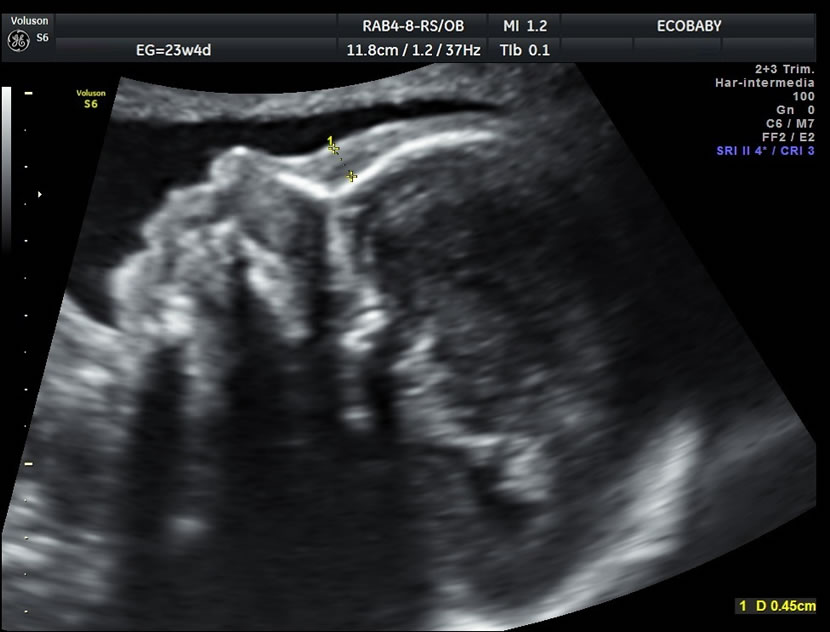

Cerebro, cuello, cara, tórax, corazón (diferentes cortes que muestran las cavidades y la correcta entrada y salida de arterias y venas), abdomen (normalidad de la pared, estómago, intestino, riñones, vejiga), miembros inferiores y superiores y columna vertebral.